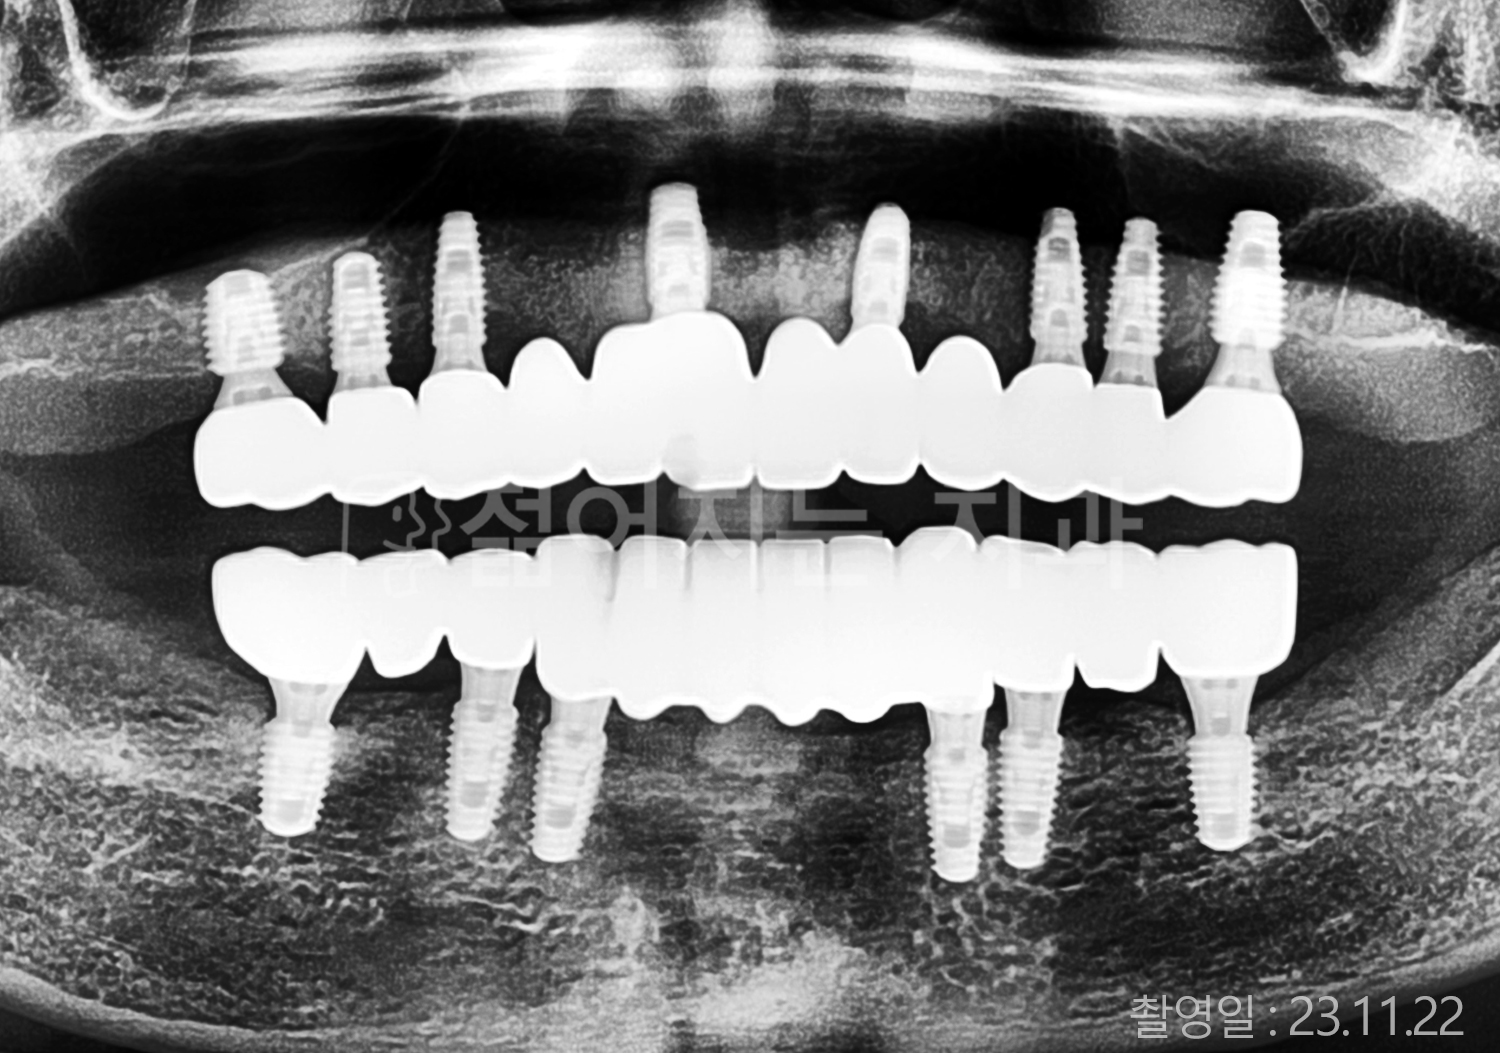

• 50대 전체치아 10개 이상 임플란트

• 50대 고혈압, 고지혈증 전체치아 10개 이상 임플란트

• 60대 고혈압, 당뇨, 고지혈증 전체치아 10개 이상 임플란트